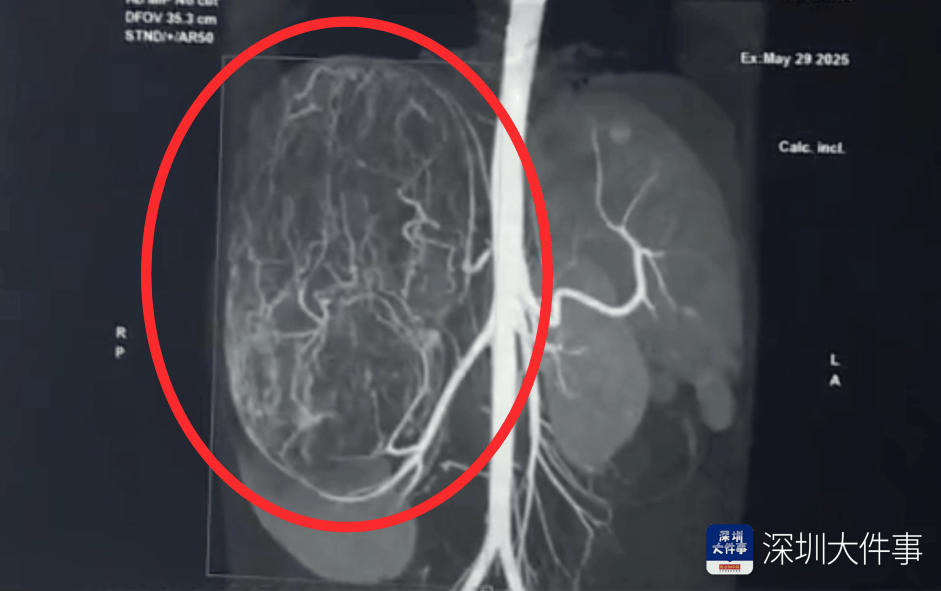

影像检查结果出来,所有人都倒吸一口冷气:一个直径27厘米(比篮球还大)的巨型肿瘤,霸占了整个腹腔右半边最新虚拟币价格。肝脏被它硬生生挤到了肚脐眼以下的位置!

肿瘤体积过大,这也意味着留给医生的手术空间实在有限,强行微创?万一瘤子破了,肿瘤扩散大出血,后果不堪设想!所以,只能通过开放手术来做最新虚拟币价格。

5月30日,医生为婷婷做手术,打开腹腔后,医生遇到了挑战:婷婷的肾动脉异于常人:正常人就1根肾动脉供血,她居然有3根最新虚拟币价格。还有一支来自腹腔干动脉,一支来自腰动脉。

这三根“命脉”就盘踞在巨大的瘤体上,稍有不慎,剪错一根,就可能引发大出血最新虚拟币价格。

手术团队屏气凝神,抽丝剥茧,一根一根精准找到、小心分离、稳稳阻断……经过3个多小时的精密操作:重达2.43公斤直径达27厘米的“巨无霸”肿瘤被完整端出最新虚拟币价格。周围需要清扫的淋巴和脂肪组织也被清除。